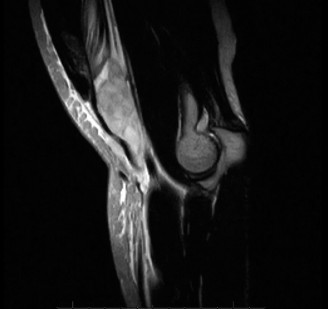

The correct answer is (B). A pectoralis major muscle (PMM) tear or rupture usually occurs in weight-lifters while performing the bench press, but it can occur during

any activity in which the arm is extended and externally rotated while under maximal contraction (eccentric loading force). Patients often present with pain, swelling, ecchymosis, weakness and loss of the axillary fold in the acute setting. In the chronic setting, the swelling and ecchymosis have typically subsided. They may report an audible pop or a tearing sensation. On examination, there can be an apparent continuous muscle or tendon that is mistaken for an intact PMM tendon, but this represents the fascia of the PMM that is continuous with the fascia of both the brachium and the medial antebrachial septum. This continuous fascia will examine as a cord-like structure as shown in Figure 2–78.

Figure 2–78

The sternocostal portion of the muscle is injured more often than the clavicular. A rotator cuff tear and biceps tendon injury are unlikely given the mechanism of injury and physical examination findings. In addition, this patient is young for a rotator cuff tear. Poland syndrome is the congenital absence of the PMM. Pectoralis minor muscle rupture is scarcely reported and would not have the same history and physical examination findings.